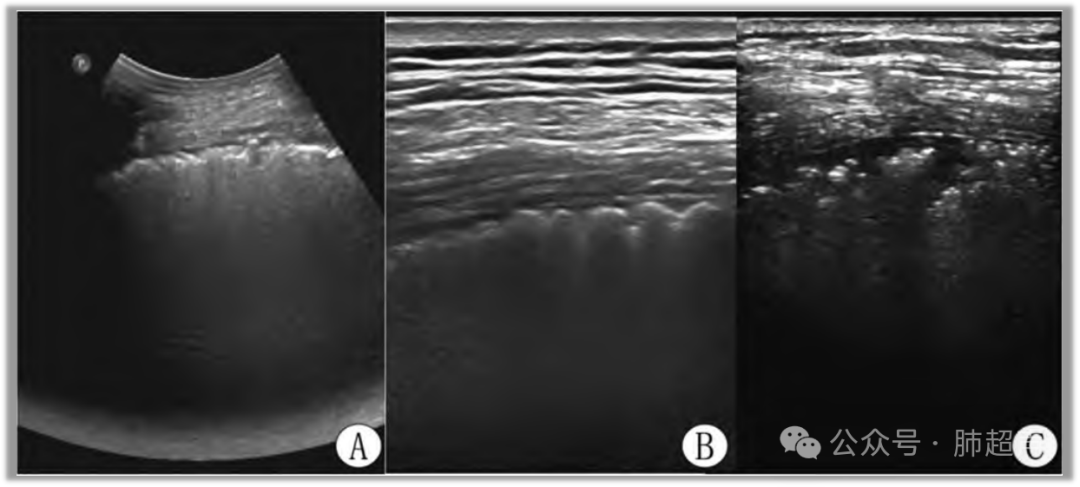

肺实变随吸气可转换为B线或A线 (图1),系因气体含量增加导致肺超声征象发生变化,提示该区肺支气管—肺泡气道通畅,肺泡存在充气复张潜能,可排除阻塞性肺不张。

图1  吸气过程诱发肺超声气—液往返征示意图

注:A. 呼气末; B. 吸气末